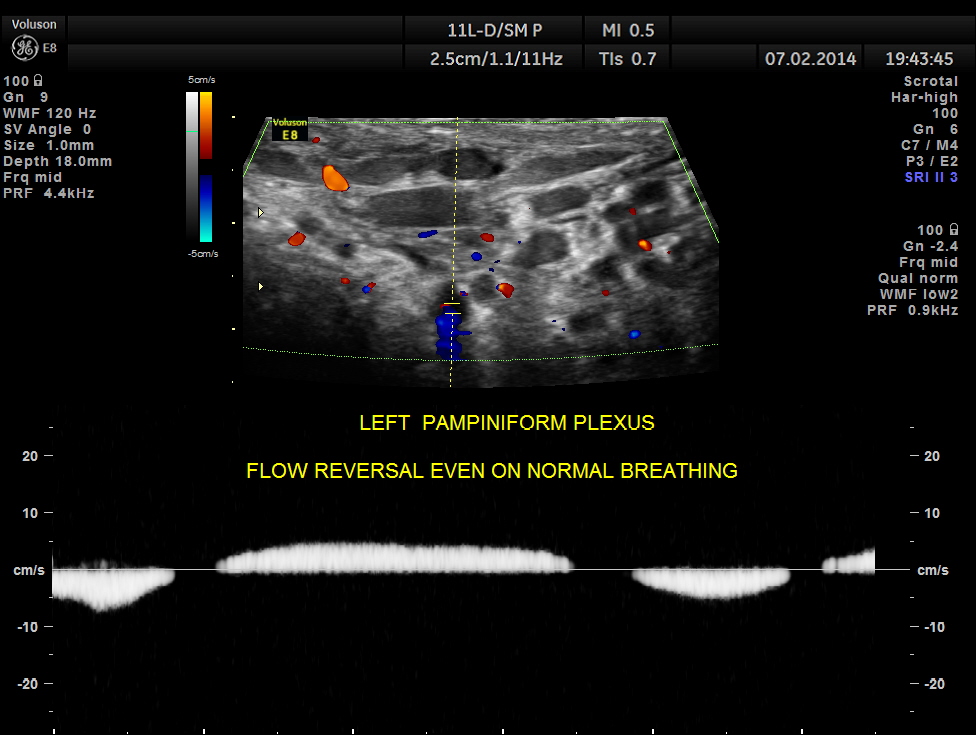

NORMAL RESPIRATION CAUSES FLOW REVERSAL.

VALSALVA causes an exaggerated response.